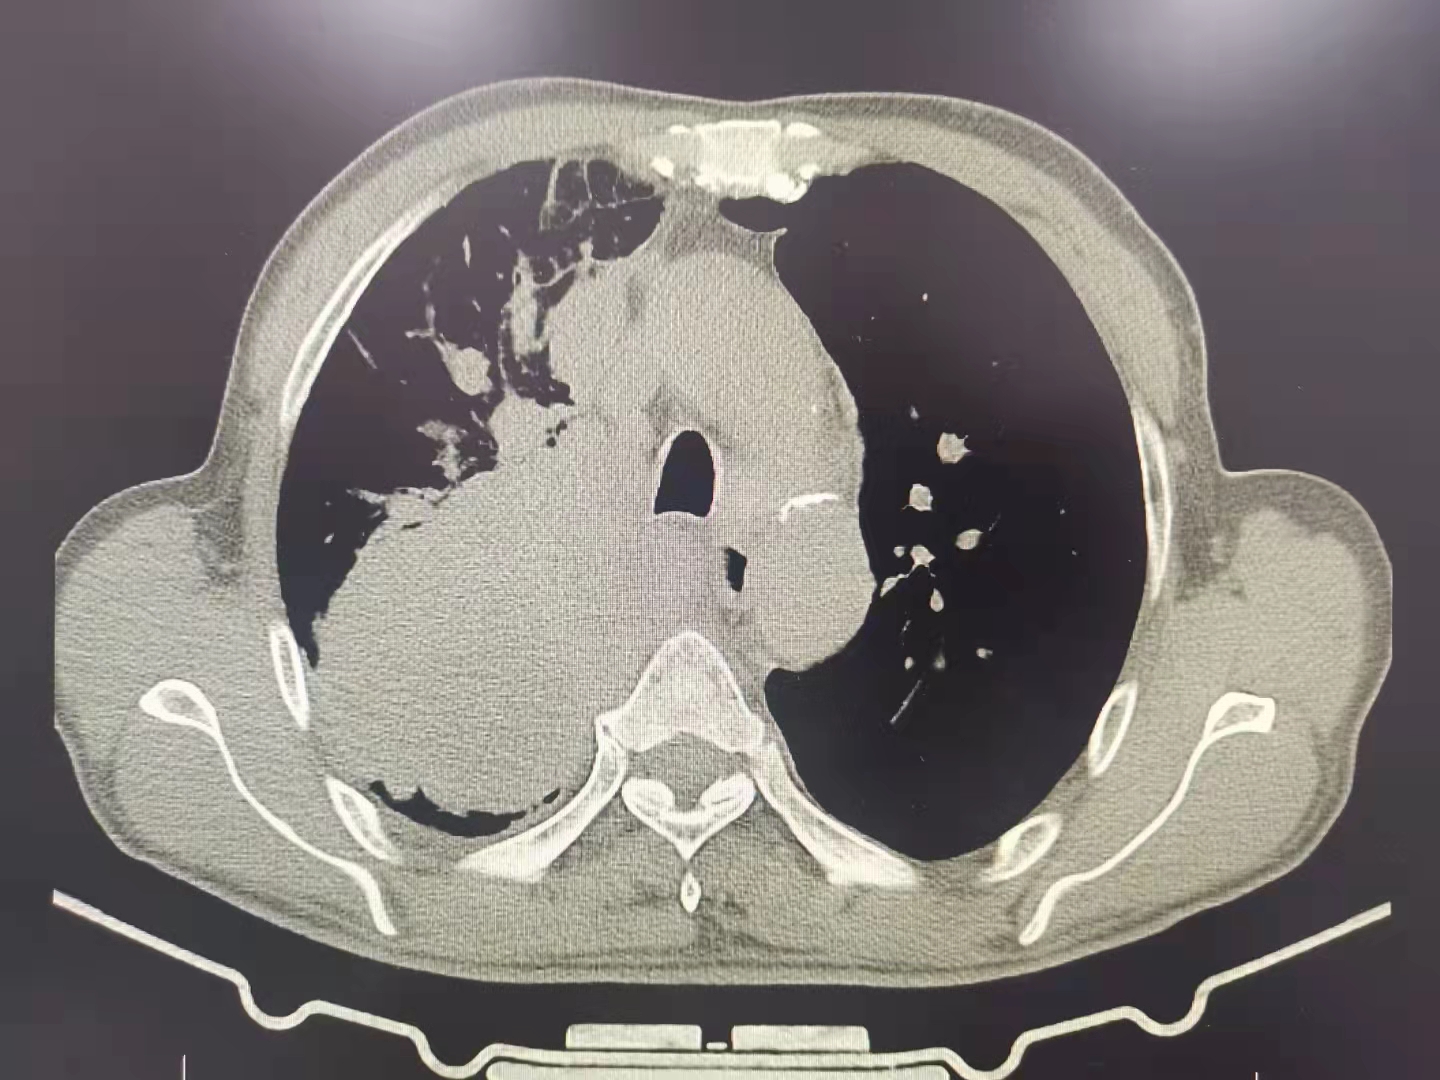

今日再次為一例肺部占位合并氣道內(nèi)腫瘤的患者施行支氣管鏡下的介入手術(shù),術(shù)前呼吸困難、心律失常二聯(lián)律,術(shù)后患者呼吸困難明顯緩解,且心律失常得以糾正,效果立竿見影。但是影像學(xué)的巨大腫塊,還需要結(jié)合病理分型采取恰當(dāng)?shù)木C合治療手段來減緩和控制疾病進(jìn)展。呼吸介入,我們團(tuán)隊一直在前進(jìn)中。